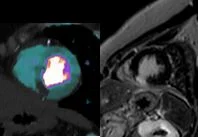

My oh MI!

Gopal Punjabi

September 18, 2018